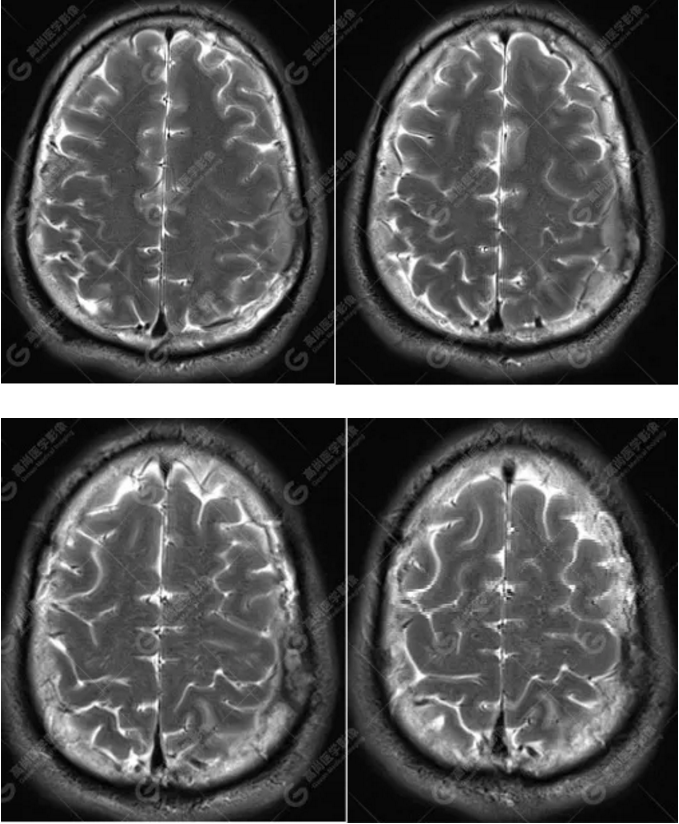

MR圖像

左側額頂部顱骨骨質破壞并相鄰硬腦膜增厚強化,考慮Rosai Dorfman?。≧DD)可能,需與朗格漢斯細胞組織細胞增生癥鑒別。

總之,顱內RDD是一種罕見的硬腦膜良性病變,若 MRI發(fā)現(xiàn)顱內基于硬腦膜扁平或匍匐生長的孤立或者多發(fā)腫塊,CT 檢查未見鈣化,而MR檢查T2WI及 DWI呈低信號,增強明顯均勻強化,應考慮到 RDD 的可能。